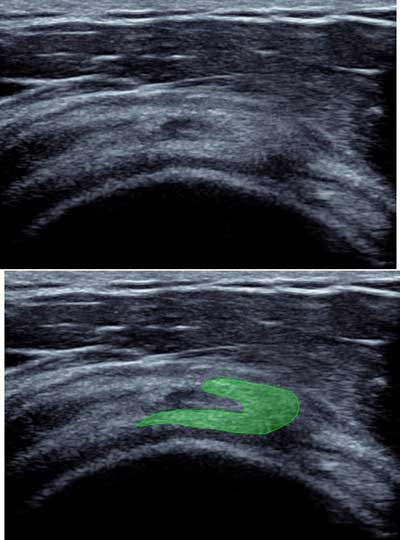

Figure 11

Sagittal view of the rotatorcuff with “coma” appearance of the myotendinous junction of the supra spinatus.